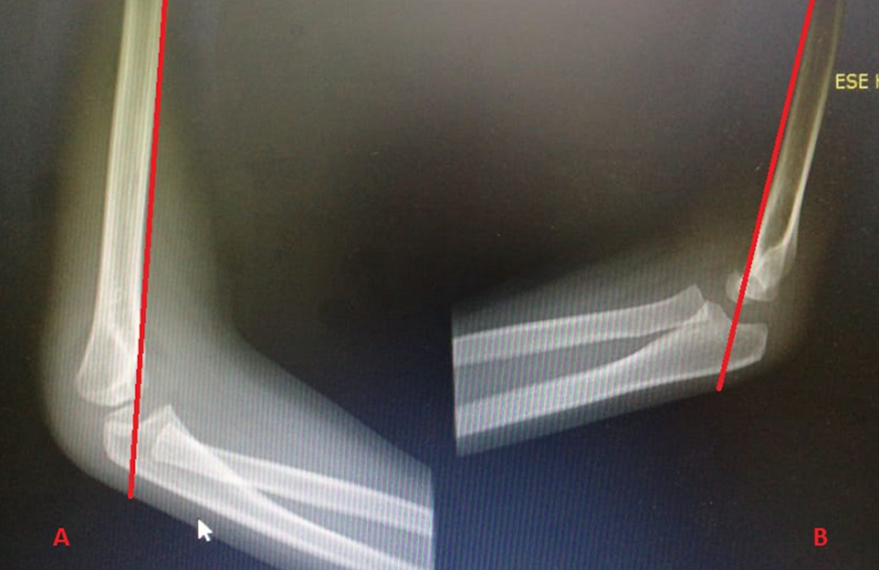

En la Figura 3 y en la Figura 4 se pueden ver imágenes de la clasificación, que se divide en3:

· Tipo I: no desplazada, se puede ver la línea de fractura o el signo de cojinete graso en la radiografía lateral.

· Tipo II A: con desplazamiento posterior, con periostio conservado. La angulación normal del capitellum (30°) puede disminuir y la línea humeral anterior que normalmente secciona al capitellum en su tercio medio puede ubicarse en el tercio distal o, incluso, no atravesarlo.

· Tipo II B: fractura II A que además tiene un componente rotacional del desplazamiento o traslación de los fragmentos.

· Tipo III: se pierde todo contacto del periostio, lo que hace la fractura inestable con alto riesgo de lesión neurovascular o de tejido blando. Se subdivide en A si tiene desplazamiento posteromedial o B si tiene desplazamiento posterolateral.

· Tipo IV: fractura tipo III que además tiene inestabilidad rotacional con mayor riesgo de lesiones asociadas.